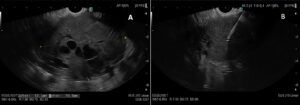

An endoscopic ultrasound (EUS) was performed for further characterization and tissue sampling was done using a fine 22 G needle biopsy (FNB). The referred lesion appeared hypoechoic and heterogeneous with internal anechoic areas (Fig3).

Figure 3: EUS shows a hypoechoic and heterogeneous mass with internal anechoic areas (A). Tissue sampling was performed using 22 G fine needle biopsy (FNB) (B)

Cross-sectional imaging frequently demonstrates an ill-defined, hypodense mass with heterogeneous enhancement and features of vascular encasement or invasion of nearby structures2. Endoscopic ultrasound (EUS) is highly sensitive for detecting and characterizing pancreatic lesions and allows for fine-needle aspiration or biopsy, which remains the gold standard for diagnosis3. In this patient, EUS demonstrated a heterogeneous, hypoechoic lesion with central anechoic areas, and histopathology confirmed PDAC.